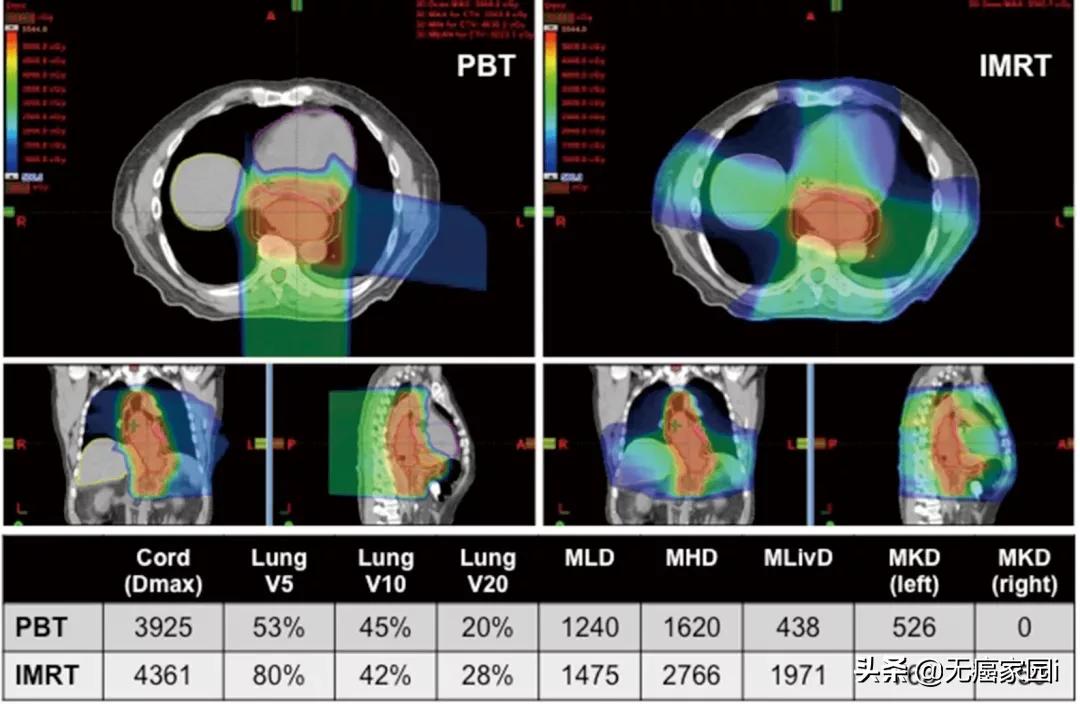

据《胃肠肿瘤学》杂志刊登的一篇关于各项放疗技术治疗食管癌患者的剂量优势的文章显示,与3D适形放疗(3DCRT)相比,IMRT改善了器官的剂量分布;治疗计划和剂量学的比较研究进一步显示,与3DCRT和IMRT相比,质子治疗可显著降低心脏和肺的照射剂量。 质子治疗可最大程度地保护心脏前部组织,减少心脏的照射剂量,具有明显的临床优势。(想了解质子治疗请咨询无癌家园医学部)

图为质子治疗与IMRT治疗食管癌的剂量学比较,左为质子治疗,右为调强放疗

(注:Dmax,最大点剂量;Vx,体积乘以Gy的x剂量;MLD,平均肺部剂量;MHD,平均心脏剂量;MLivD,平均肝脏剂量;MKD,平均肾脏剂量)